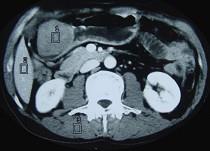

问题 女性,42岁,腹痛、黑便1周,CT扫描见胃窦部圆形块影,最佳的诊断是 ( )

选项 A.胃窦平滑肌瘤 B.胃癌 C.胃淋巴瘤 D.胃窦神经纤维瘤 E.胃内异物

答案 D